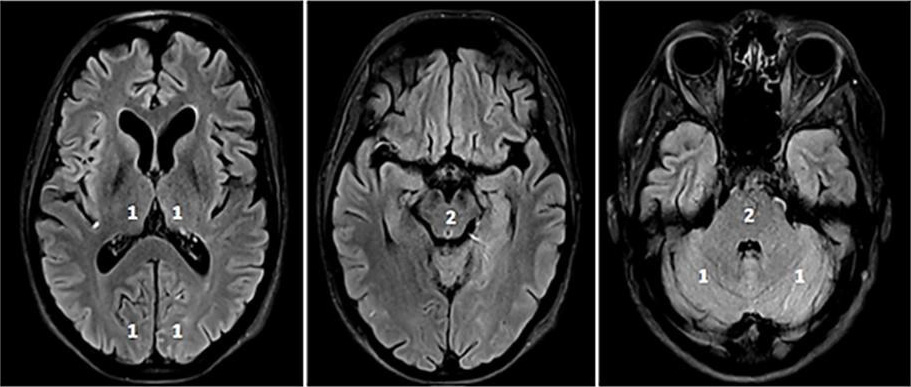

The use of additional perfusion imaging (CT-P or MR-P) in the early time window (within 6 hours of symptom onset) is controversial and is not recommended in routine clinical practice [34, 35, 36, 37]. Perfusion imaging can be used to estimate the infarct core and potential tissue at risk (penumbra). Fig. 2 (Ref. [38, 39, 40]) illustrates CT-P parameters and potential thresholds for both the infarct core and penumbra. These thresholds are debatable and not universally accepted, and may change with the duration of symptoms [38, 40]. In an early time-window, CT-P can overestimate the infarct core, possibly because of a lack of contrast arrival overall [41]. In a pooled analysis from the Highly Effective Reperfusion evaluated in Multiple Endovascular Stroke Trials (HERMES) collaboration, adding CT-P in an early time window has not been found to be associated with functional outcomes [37].

Fig. 2.CT-Perfusion. NCCT ASPECTS 10 (A). CT-A with M2-occlusion (B).

Interpretation of CT-P: the cerebral blood volume (CBV) is symmetrical without a

regional decrease (C). Cerebral blood flow (CBF) is reduced in the posterior MCA

territory on the left (D). The mean transit time (MTT) of the contrast agent (E)

and Tmax (time to maximum; time delay between the contrast agent arrival in the

proximal large vessel arterial circulation and the brain parenchyma perfusion

[F]) are prolonged. The infarct core in CT-P shows a markedly reduced CBF (